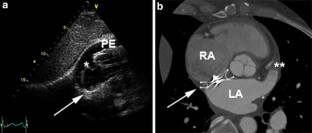

Very late cardiac tamponade following successful transcatheter closure of an atrial septal defect with the Amplatzer septal occluder

We thank S. Ullrich, Institute of Radiology, Triemli Hospital Zurich, Switzerland for providing the CT image shown in Fig. 1b, and F. Osann for expert patient care in the emergency room.